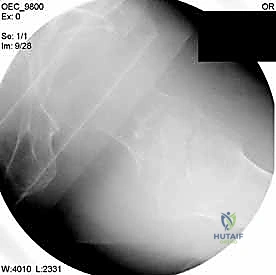

التصوير الطبي المتقدم

- الأشعة السينية (X-rays): هي المعيار الذهبي الأولي. يتم أخذ صور من الأمام للخلف (AP) وصور جانبية (Lateral) للحوض والورك المصاب. تكشف هذه الصور عن موقع الكسر، نوعه (بسيط أم مفتت)، ودرجة الإزاحة.

2. الرد المغلق تحت جهاز الأشعة (Closed Reduction)

قبل إجراء أي شق جراحي، يقوم الدكتور هطيف بسحب الساق وتدويرها بمهارة فائقة لإعادة العظام المكسورة إلى مكانها الطبيعي (المحاذاة التشريحية). يتم التأكد من ذلك باستخدام جهاز الأشعة السينية المتحرك داخل غرفة العمليات (C-Arm Fluoroscopy). هذه الخطوة حاسمة، فالرد الجيد يعني التئاماً ممتازاً.

مجموعة من الصور الإضافية التي توضح مراحل دقيقة من العمل الجراحي المعقد الذي يجريه الأستاذ الدكتور محمد هطيف لضمان أعلى درجات الدقة الميكانيكية الحيوية: